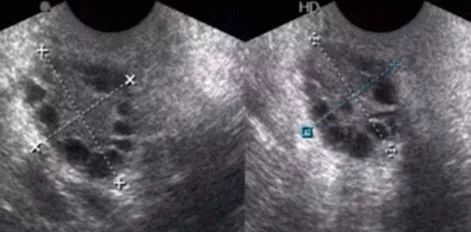

因此正确评估卵巢储备功能就显得尤为重要,有生育需求的患者可以先去医院进行相关检查,评估卵巢储备功能。目前临床上常用的卵巢储备功能评估的指标:①年龄; ②基础性激素及细胞因子水平测定; ③影像学指标: 超声检查卵巢大小、基础窦卵泡数目和卵巢基质血流等。